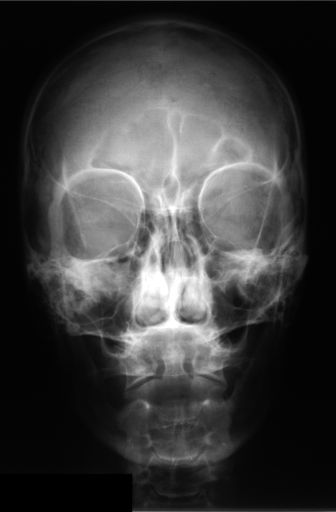

More information on the IRMA database and code can be found in [21, 23, 22]. IRMA dataset offers 12,677 images for training and 1,733 images for testing. Figure 3 shows some sample images from the dataset long with their IRMA code in the format TTTT-DDD-AAA-BBB.